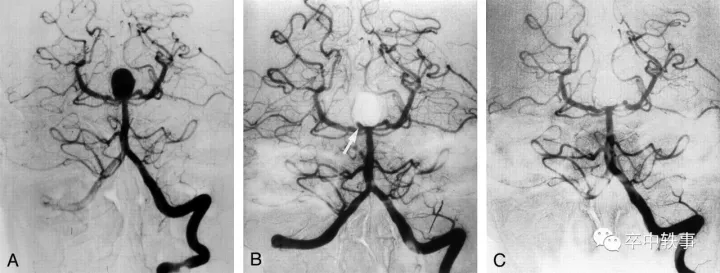

从1990年起人们可以介入栓塞颅内动脉瘤了 (上图)。开刀夹闭动脉瘤手术越来越少了。